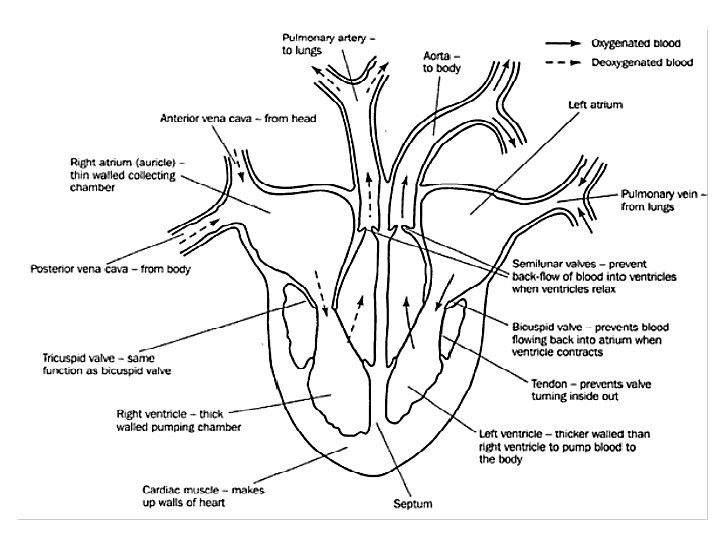

Internal Structure of the Heart • The heart has four chambers: the left and right atria (1 atrium) and the left and right ventricles. • The following diagram is the internal structure of the heart.

• Remember that the left side (RED) accepts and pumps out oxygenated blood. • The right side of the heart (BLUE) accepts and pumps out deoxygenated blood.

VALVES IN THE HEART • There are four valves in the heart: – Two semilunar valves, (one in each side of the heart). – Two atrioventricular valves (one each found between the atria and ventricles on both sides of the heart). – The function of the valves in the heart are to direct the flow of blood in only one direction.

The Heart Summary Fist sized; found on left side. Consists of cardiac muscle fed by coronary arteries Left side pumps O 2 -rich blood to head and body; Right side pumps O 2 -poor blood to lungs Two upper atria, two lower ventricles Septum separates left and right sides ensuring diffusion gradient • Left ventricle thicker to pump blood all over body • Valves prevent back-flow of blood • • •

Path of Oxygenated Blood • Pulmonary vein left atrium • Through mitral valve down into the left ventricle. • The ventricle then contracts forcing the mitral valve closed and opening the semilunar valve. • The blood then flows up into the aorta and around the body.

Path of Deoxygenated blood • Vena cava right atrium • Through tricuspid valve right ventricle. • Ventricle contracts, tricuspid valve closes, semilunar valve opens. • Blood flows to the pulmonary artery lungs.